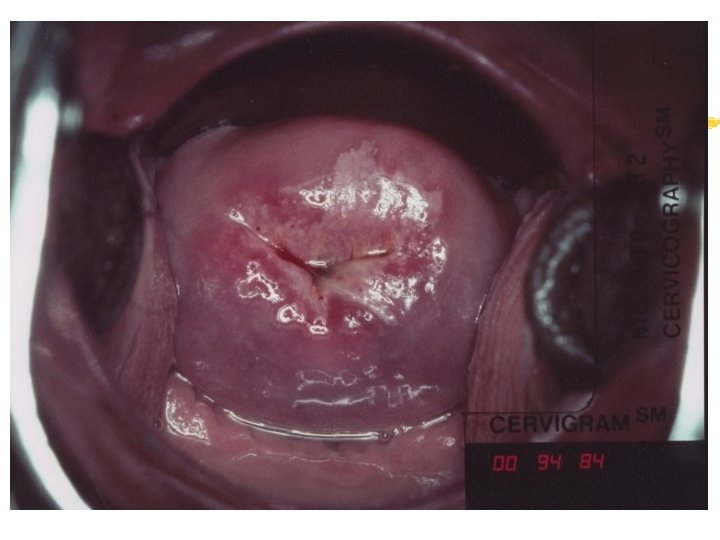

Normal Cervix:

Cervicography: This is NOT Colposcopy High-quality colposcopic-type photography of the cervix Cervicoscope - Hand-held camera with a macrolens and a ring-flash Cervicogram - 35 -mm photo slide is taken Principles Recognition of lesions by means suitable magnification and illumination Fix up the problems of colposcopy 1. a less expensive form 2. noninvasive method 3. do not require expert skill

Procedures of cervicography A) Taking a 35 -mm cervicogram (1) Insert speculum and open as wide as possible … expose an entire cervix and upper vagina (2) Apply first application of 5% acetic acid by dabbing … cleanse the cervix of blood and mucus (3) View the cervix through the cervicoscope … allows time to begin taking epithelial change (4) Apply second application of acetic acid. (5) Take two cervicogram pictures B) Developing the images C) Interpreting a magnified image that was projected on the screen (1) Negative if no definitive lesions are visible (2) Atypical if there was evidence of acetowhite lesion of doubtful significance (3) Positive if there was evidence of a minor or major-grade lesion or cancer